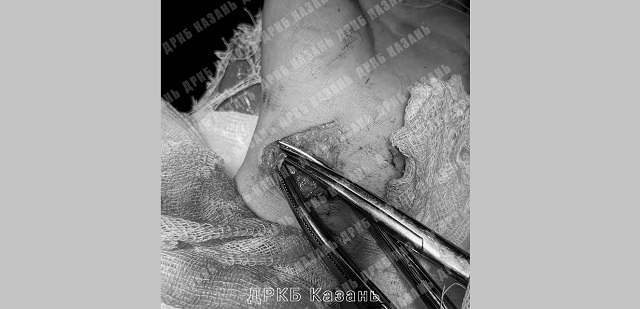

В Казани в Детскую республиканскую клиническую больницу (ДРКБ) поступил истекающий кровью ребенок, который неудачно упал на осколки разбитой бутылки, передает пресс-служба медучреждения.

Осколки повредили лучевую артерию (на предплечье), в результате чего ребенок потерял литр крови. Доставленного из района в ДРКБ маленького пациента экстренно прооперировали, и сейчас его жизни ничто не угрожает.

Фото: телеграм-канал «ДРКБ Казань»